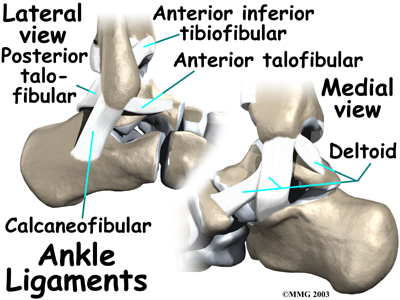

Ligaments on both sides of the ankle joint help hold the bones together. make up the lateral ligament complex on the side of the ankle farthest from the other ankle. (Lateral means further away from the center of the body.) These include the anterior talofibular ligament (ATFL), the calcaneofibular ligament(CFL), and the posterior talofibular ligament (PTFL). A thick ligament, called the deltoid ligament, supports the medial ankle (the side closest to your other ankle).

Ligaments also support the lower end of the leg where it forms a hinge for the ankle. This series of ligaments supports the ankle syndesmosis, the part of the ankle where the bottom end of the fibula meets the tibia. support this area. The ligament crossing just above the front of the ankle and connecting the tibia to the fibula is called the anterior inferior tibiofibular ligament (AITFL). The posterior fibular ligaments attach across the back of the tibia and fibula. These ligaments include the posterior inferior tibiofibular ligament (PITFL) and the transverse ligament. The interosseous ligament lies between the tibia and fibula. (Interosseous means between bones.) The interosseus ligament is a long sheet of connective tissue that connects the entire length of the tibia and fibula, from the knee to the ankle.